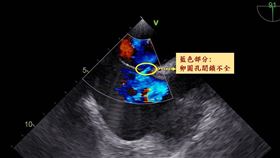

卵圓孔閉鎖不全

29歲工程師突失明 心臟有個洞造成

新竹29歲林姓工程師日前工作時突然發現右眼視力模糊,...